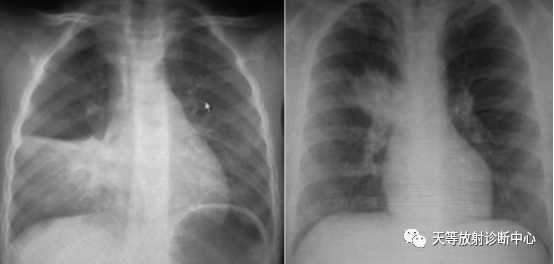

上图:左边病例:支原体肺炎,右侧肺炎,肺不张。

右边病例:两侧肺门影增大增浓。

病例来源:庄丽霞 张 芬.小儿肺炎支原体感染321例临床和影像学特点分析[J].福建医药杂志.2020.42(1):91-93.